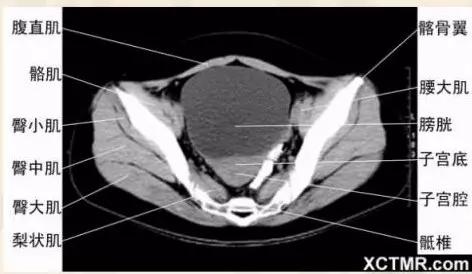

女性盆腔CT断层